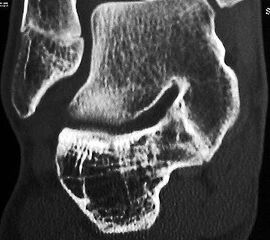

Z.n. Distorsion des Fußes mit „Ruptur“ der (vorbestehenden) talocalcanearen Coalitio. Die Wassereinlagerung in den an die Coalitio angrenzenden knöchernen Bezirken ist im MRT gut zu erkennen. Nach monatelangen Beschwerden spontane Besserung.

Abbildung 1

• Anhaltende Schmerzen nach vermeintlichen oder tatsächlichen Distorsionen („Aktivierung“ der Coalitio, vgl. Abb. 1)